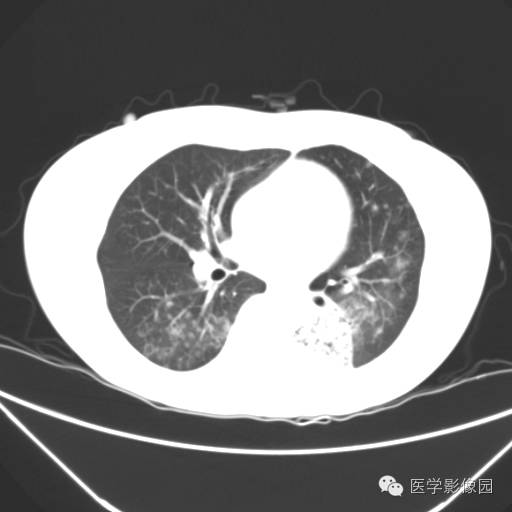

肺叶实变性支气管肺泡癌1例CT影像表现

【病例】肺叶实变性支气管肺泡癌1例CT影像表现